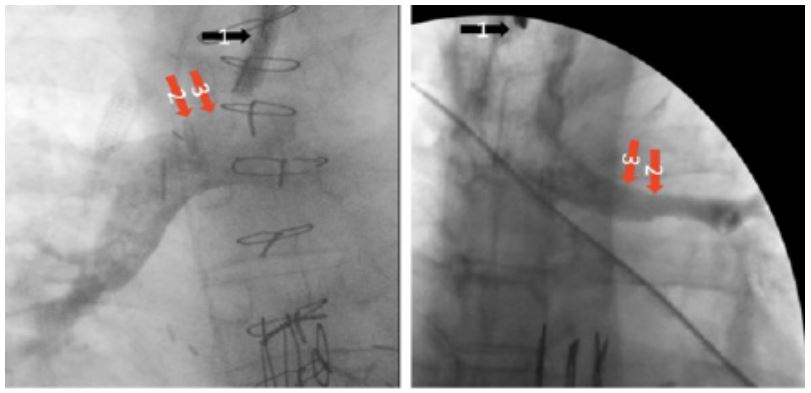

Figure 1: Fluoroscopic airway contrast images. Both images provide adescription of how we measure airway diameter using contrast. On the left we demonstrate our measuring technique in a normal anastmosis. We first measure the diameter of the scope (black arrow#1) which provides a calibration for the radiology software to calculate distance in mm. After calibration is perfomed, we measure the anastomosis (redarrow#2) from end-to-end and repeat this for the proximal airway (red arrow#3). On the right, we demonstrate a stenotic anastmosis.